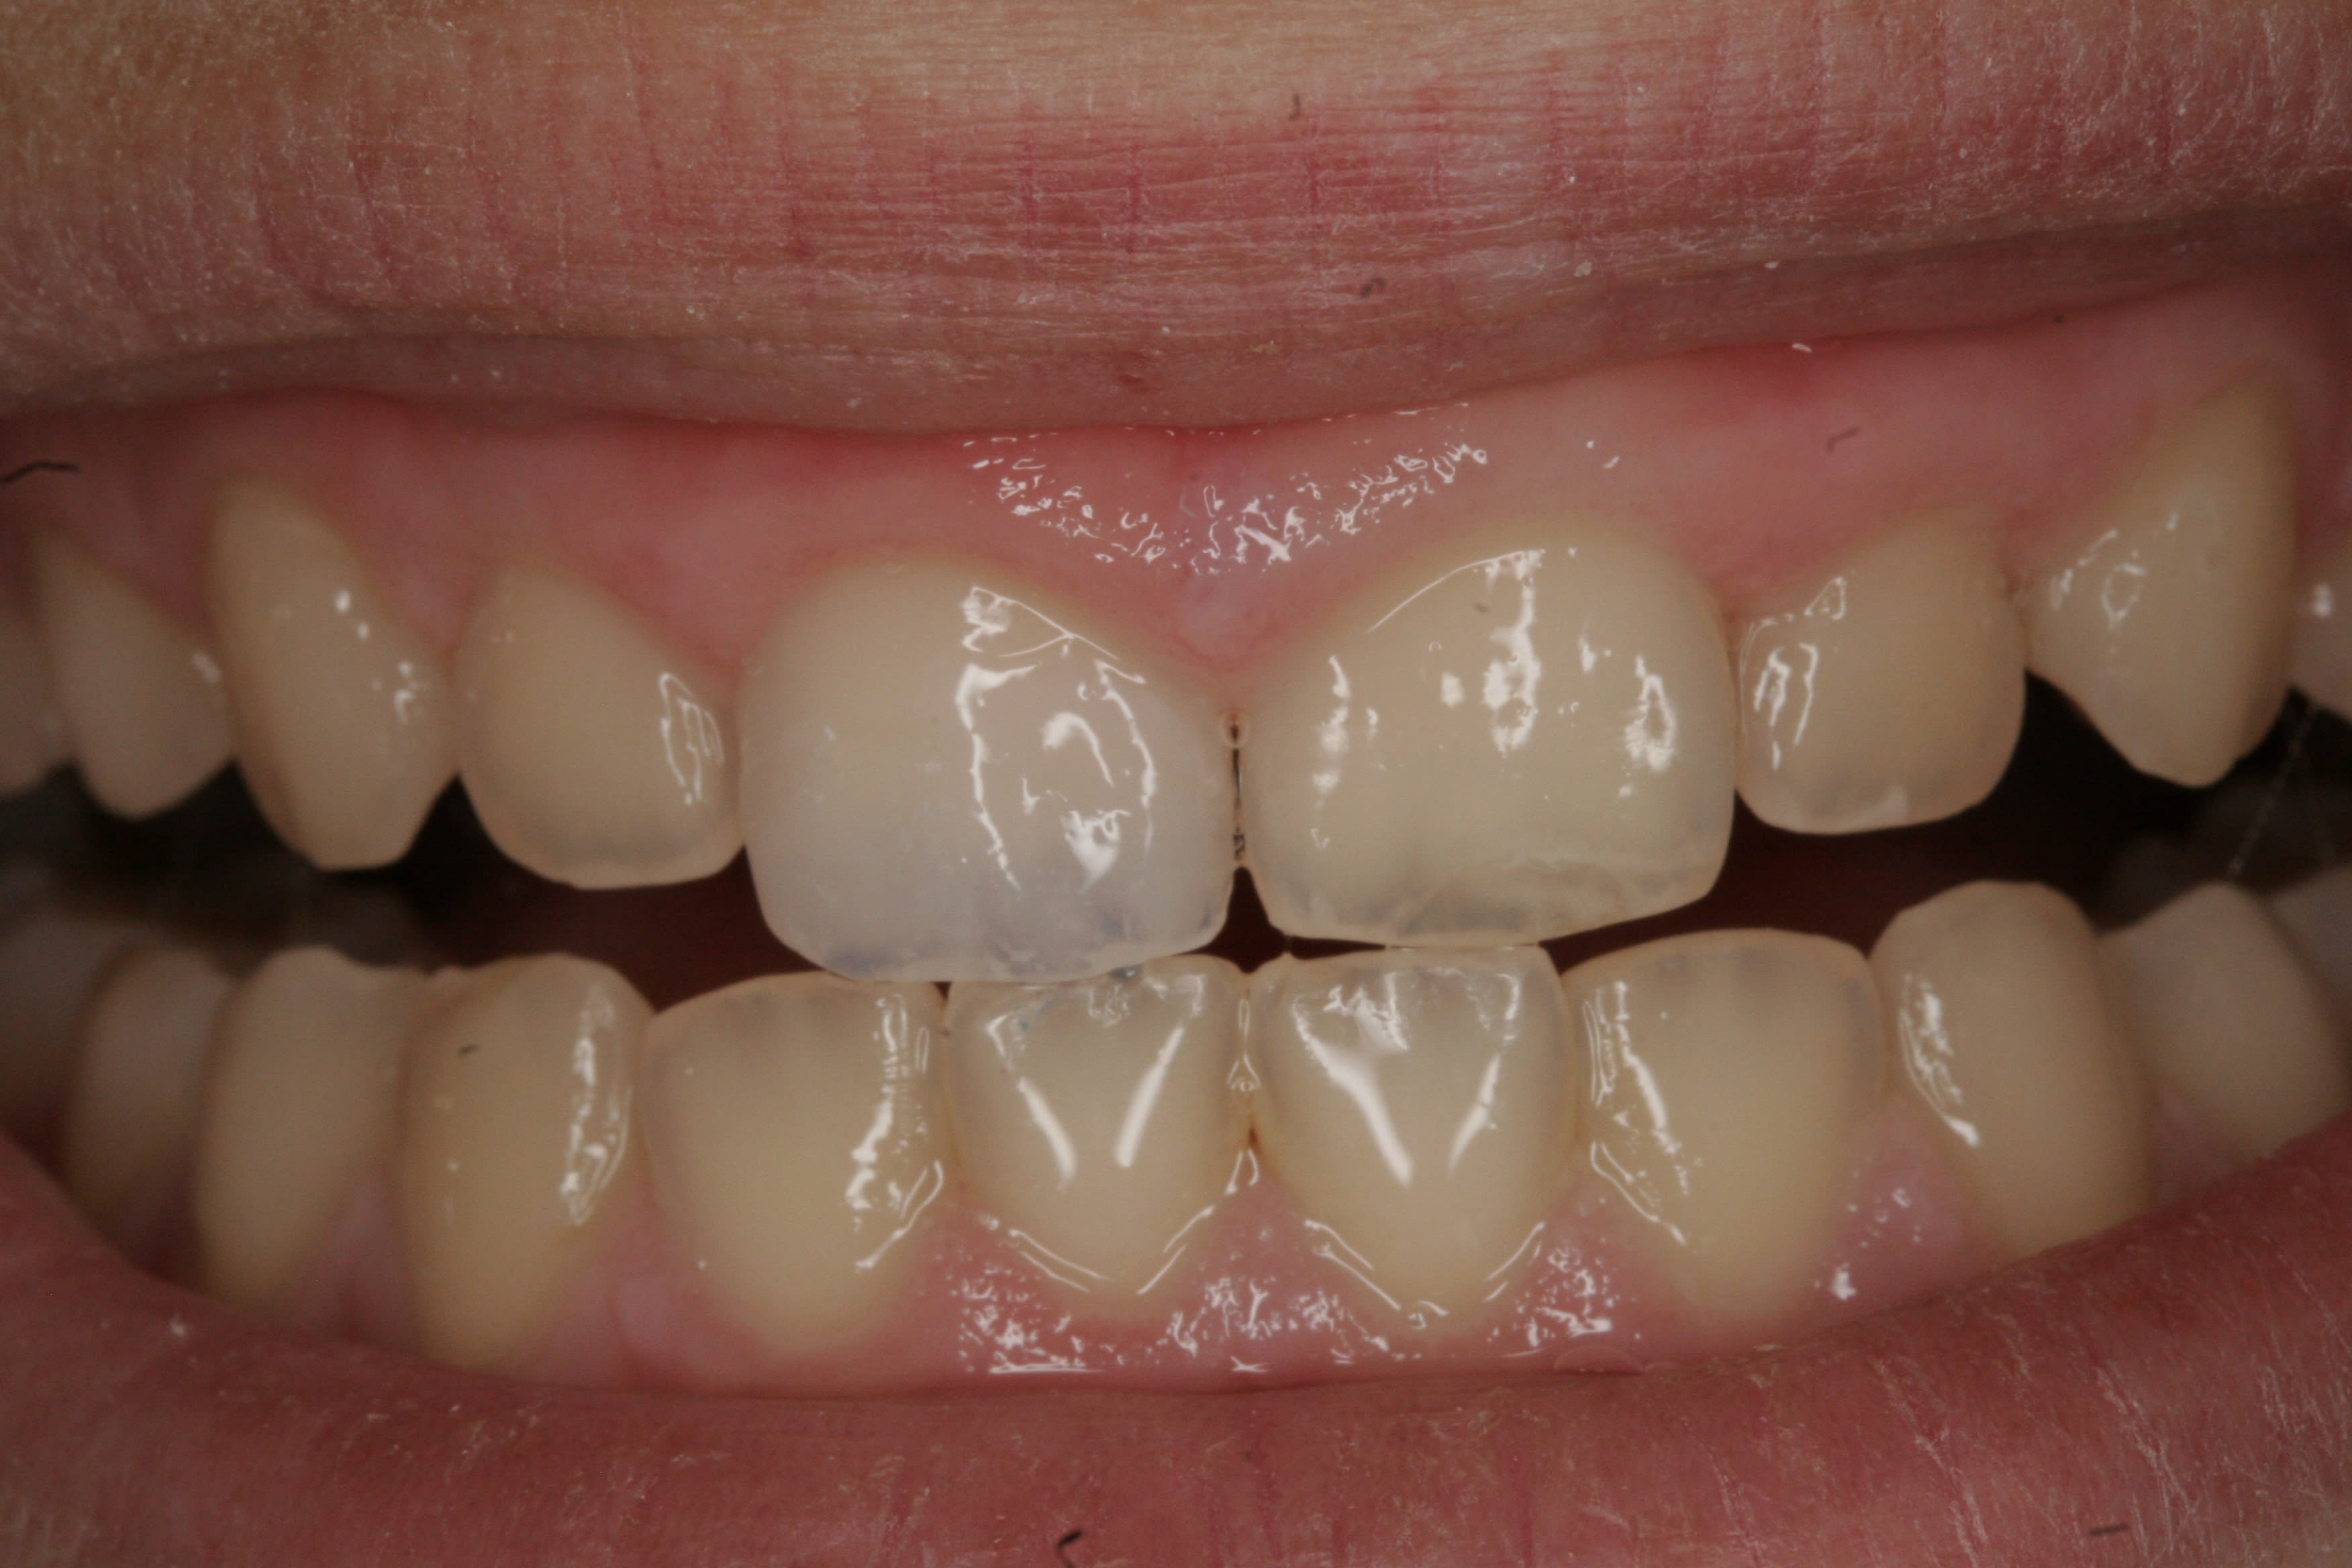

Un p'tit dernier pour la route, avec un visuel à 6 mois

C'est vrai que ça se salit à donf c'te saloperie, bon c'est vrai aussi qu'un p'tit polissage de 15 minutes suffit à leur redonner de l'éclat.....mais chut faut pas le dire, faudrait pas frustrer le gamin.

74 ans, une abrasion à plus de 50% sur les inf. et une putain de classe 2 compensée par une sale tendance à la propulsion pour bien niquer les faces palatines des sups et exploser les infs.

Primo en Céram j’y vais pas, comme dit Enlaye: je me cague de le faire.....,et c’est vraiment